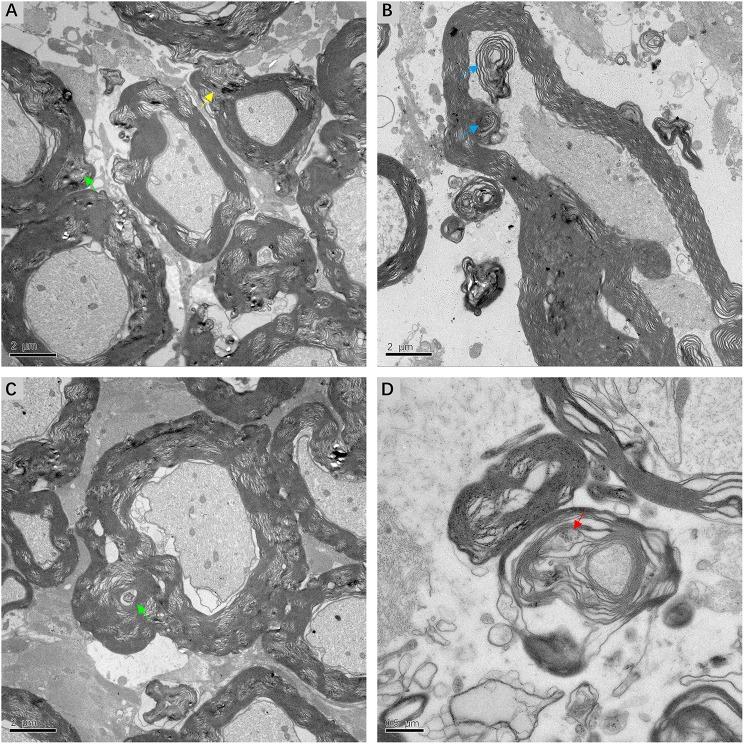

Few studies so far have focused on the retrocochlear lesions in Meniere's disease (MD). This study aims to investigate pathological alterations in the central portion of the vestibular nerve (VN) in patients with intractable Meniere's disease (MD) and to explore retrocochlear lesions and their relationship with disease severity. Eight MD patients with refractory vertigo received vestibular neurectomy via a retrosigmoid or translabyrinthine approach. Segments of VN were carefully removed and immediately fixed for histopathological examination. Five VN specimens were examined by light microscopy after hematoxylin/eosin staining; three specimens were extensively analyzed using transmission electron microscopy, to identify VN ultrastructural lesions. Correlations between lesions and patient clinical characteristics were examined. Histopathological examination revealed evidence of various types of chronic VN impairment, including the formation of corpora amylacea (CA), axon atrophy, and severe damage to the myelin sheath. Electron microscopy revealed membranous whorls within dilated Schmidt-Lanterman incisures, the formation of myeloid bodies, dysmyelination, and demyelination. Unexpectedly, we observed a positive correlation between the density of CA in VN tissue and the duration of disease, as well as the degree of hearing impairment, independent of age. Our findings indicate that deformation of subcellular organelles in the central portion of the VN is one of the key pathological indicators for the progressive severity and intractability of vertigo and support a vestibular nerve degeneration.